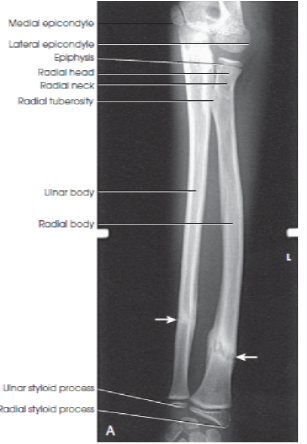

What structures are shown in an AP forearm image?

entire forearm including wrist and distal humerus.

eval - how should the proximal row of carpal bones appear in an AP forearm image?

slightly distorted

eval - What happens to the radial head, neck, and tuberosity in an ap forearm image?

they are superimposed over the proximal ulna

eval - how should the humeral epicondyles appear in an ap forearm?

they should appear without elongation or foreshortening

eval - how should the elbow joint appear in an AP forearm image if the shoulder is placed in the same plane as the forearm?

the elbow joint should be partially open

eval - what happens to the space between the radius and the ulnar space in an AP forearm image?

the radioulnar space is open